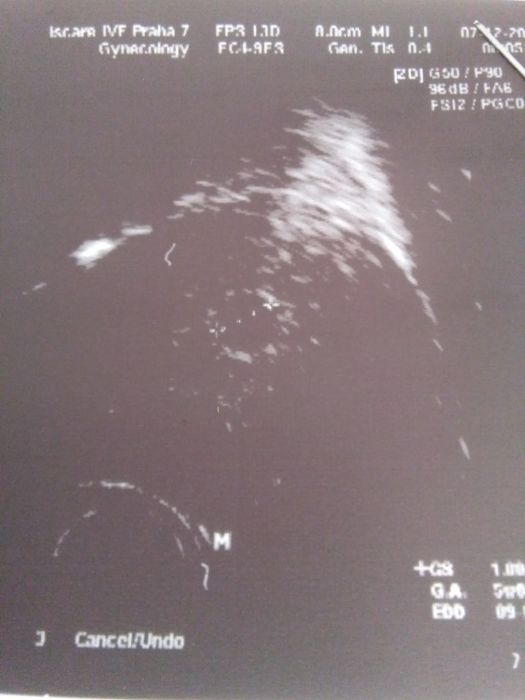

Ahoj, tak muj utz v 5+0, jen pekne spatna fotka, blbla jim tiskarna :-( ale pry to taky odpovida :-)